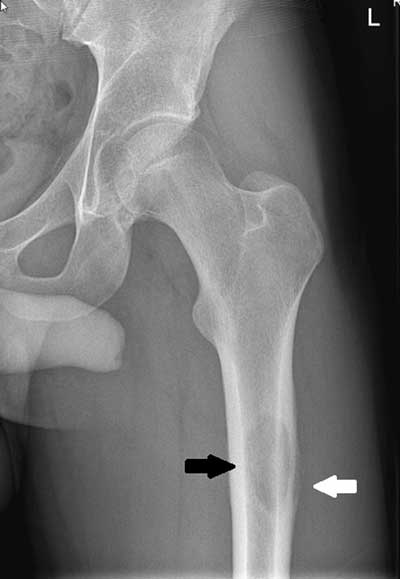

Impacted Fracture

Bony fragment is wedged into another fragment. Common in hip and shoulder fractures

The most common benign bone tumor - arises from the growth zone between the epiphysis and diaphysis of long bones (Metaphysis). Most commonly involves the lower femur or upper tibia and is capped by growing cartilage. Many time it is asymptomatic unless the affected long bone is traumatized which results in a pathologic fx. of the diseased bone.

Osteochondroma (Exostosis)